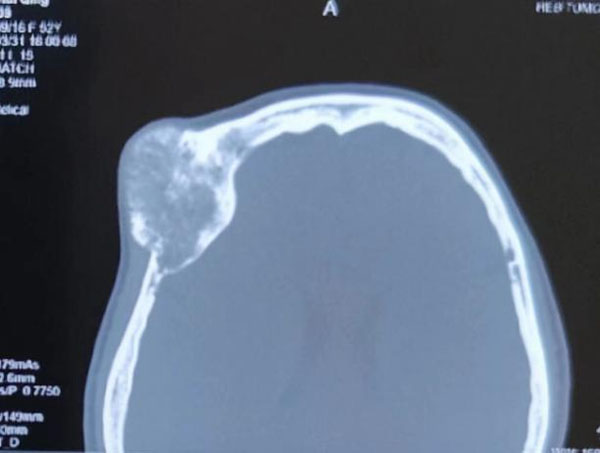

患者主因右眼视物不清伴眼球突出3年,以右眼眶内占位收入我院眼科。眼科郝玉华教授在检查中发现,患者右眼视力极低,右眼上睑下垂,眼球突出且运动明显受限。眼眶CT提示眶内巨大占位,几乎占据球后整个眶间隙。同侧额部颅骨骨质亦显示巨大肿瘤,约7*7 cm大小。患者已经有上睑下垂和视力明显下降的症状,表明肿物已经对眶上裂神经和视神经有一定压迫。

针对眶内肿瘤与颅骨肿瘤是否同源,是否需要将两部位的肿瘤同时切掉,颅骨肿瘤距离外侧眶缘较近,完整切除颅骨肿瘤后,是否会对外侧开眶造成干扰等问题,结合患者自身情况,眼科会同多科室医务人员开展联合会诊,全面评估患者情况,制定详细手术方案,向患者及家属交代手术风险并得到家属同意。手术当日,眼科郝玉华教授、魏广川主任医师带领团队联合神经外科刘英姿主任医师,顺利完整切除患者眼眶内巨大肿瘤和颅骨巨大肿瘤,患者术后恢复良好,取得满意疗效。术后病理回报:右眼眶内海绵状血管瘤,右颅骨海绵状血管瘤,骨组织内可见血管瘤样增生。